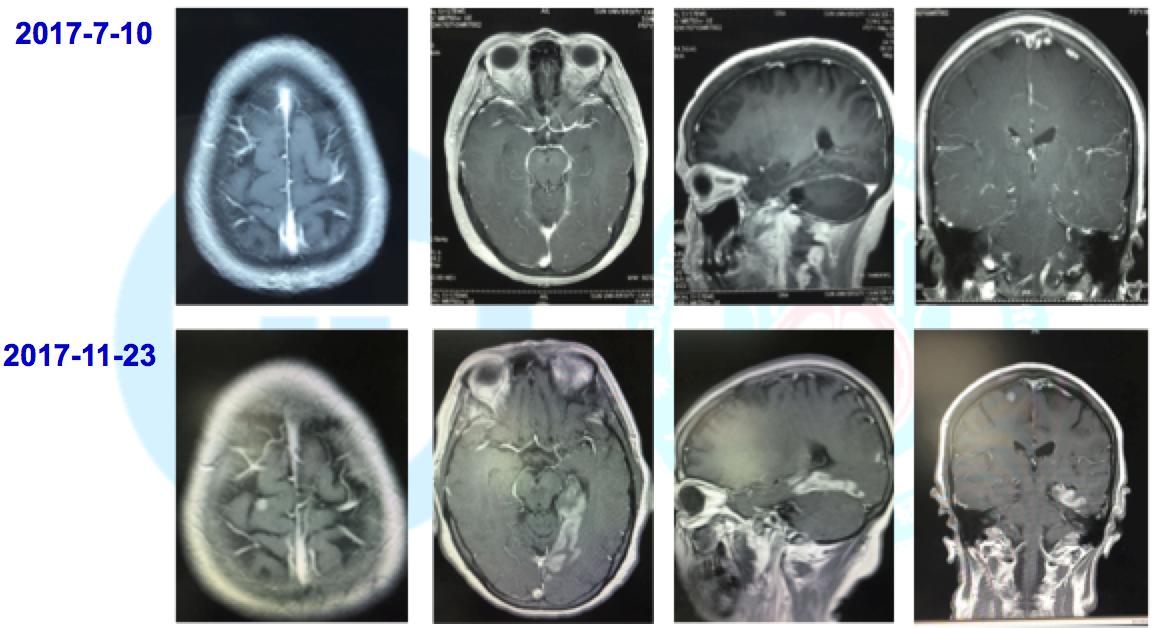

1. 一线:2017-7-22开始口服易瑞沙,2017-8-23CT示右肺病灶增大,大脑右侧额叶转移,PD,PFS=1月

3. 三线: 2017-10-18予以培美曲塞800mg+卡铂500mg化疗,出现气促,3度骨髓抑制,4度肝功能损害。2017-10-23血液NGS:ROS1基因融合,METexon16错义突变。2017-11-22MRI脑转移病灶增多,脑膜转移。2017-11-23CT左下肺病灶缩小36%。出现左足第三趾皮色发黑,PS=2分。